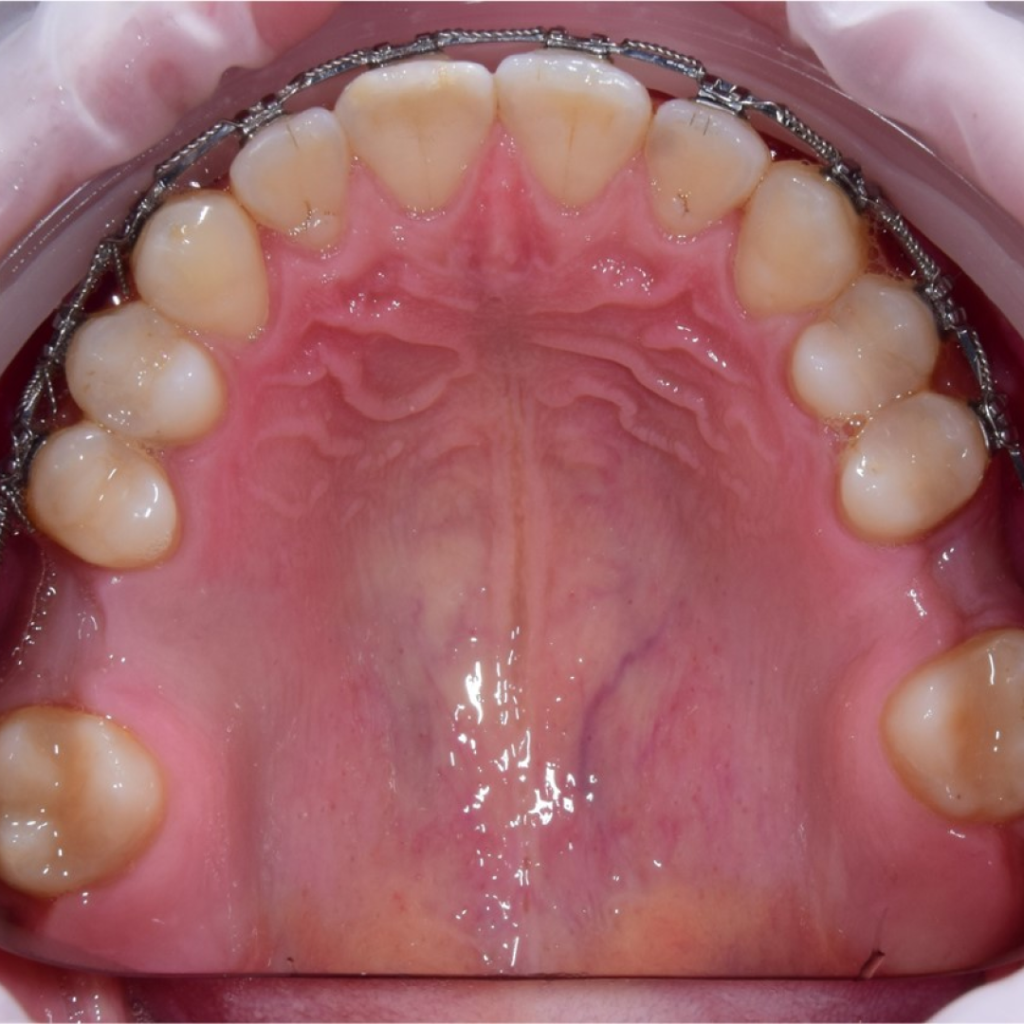

По результатам диагностики принято решение провести синус-лифтинг с помощью боров SinPro. В ходе вмешательства установлены имплантаты AnyRidge и AnyOne с первичной стабилизацией 40 Ncm.